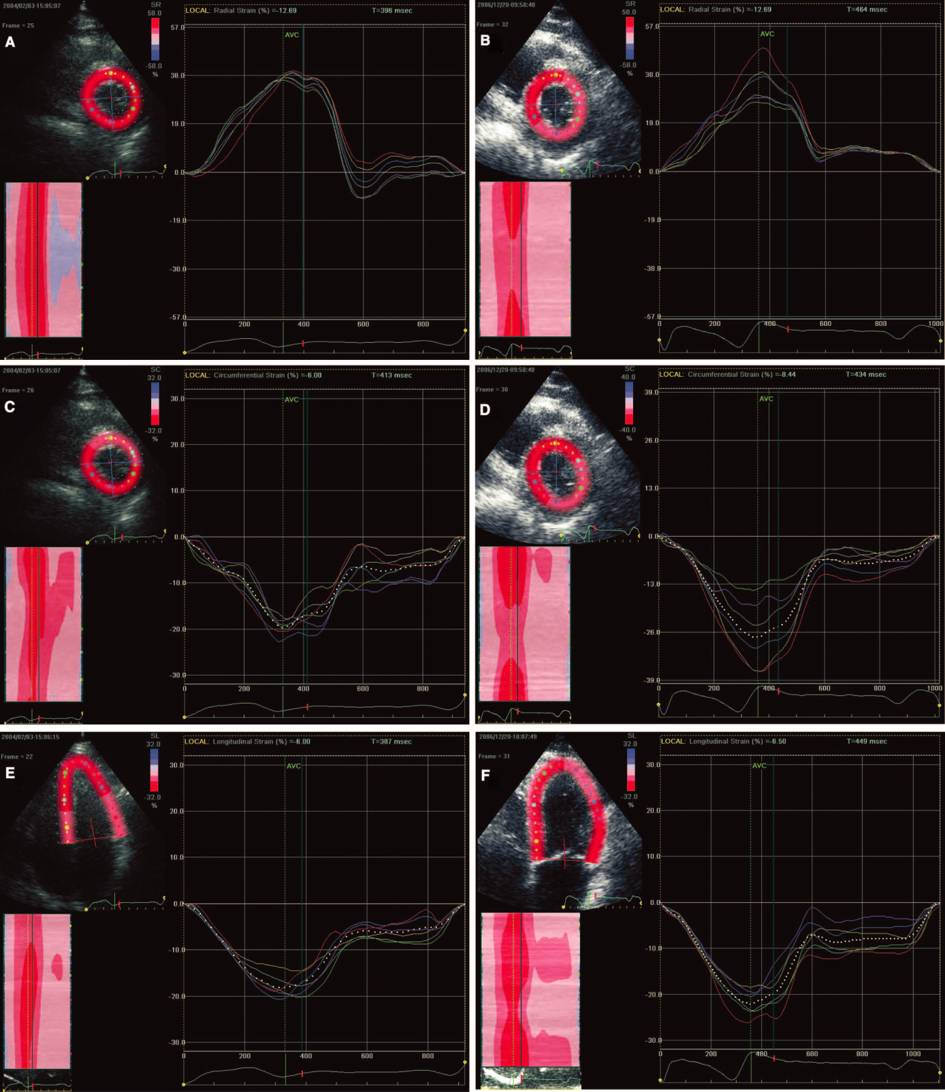

HFrEF + 房颤 导管消融

55F CAF 4 years ,CHF 6 months,NYHA III

LVED:58mm EF:28%

Ablations: PVIs 、 Roof、MI、CTI (2C3L)

6 Months Post Ablation

SHFM 消融前(上)后(下)